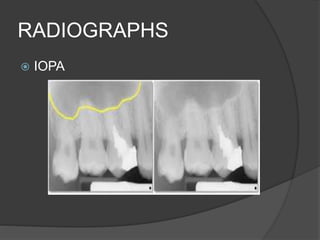

RADIOGRAPHS

 IOPA

 PANOROMIC RADIOGRAPH

 CT

Diagnosis

 Periapical radiographs

 A variation in bone density

 Presence of maxillary sinus and its bony septa

as well as zygomatic and palatal processes

 Multiple radiographic angles

 Thorough clinical examination